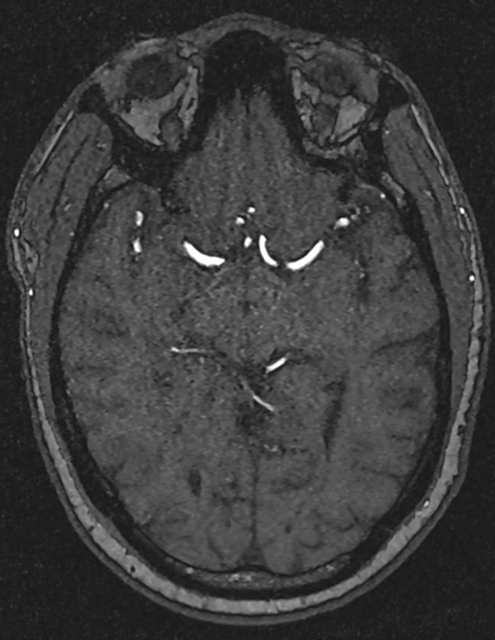

M. C., 45 ans, consulte au mois d’avril en cabinet de neurologie. Il a une sensation de vertiges et de vision double.

Le patient rapporte depuis trois semaines une diplopie lorsque ses deux yeux sont ouverts, qui disparaît à l’occlusion d’un œil. Il rapporte aussi une sensation d’instabilité à la marche avec une faiblesse de l’hémicorps gauche qui s’aggrave progressivement. Il ne décrit pas de sensation de rotation de lui-même ou de la pièce. Il a vu un ORL qui a prescrit un traitement symptomatique des vertiges, sans efficacité, raison pour laquelle il vous consulte.

– sensibilité : hypopallesthésie distale des membres inférieurs, ataxie proprioceptive aux quatre membres mais prédominant à l’hémicorps gauche, nettement aggravée à la fermeture des yeux. Pas d’hypoesthésie à la piqûre ;

– diplopie binoculaire sans paralysie oculomotrice. Pas d’autre anomalie à l’examen des paires crâniennes.